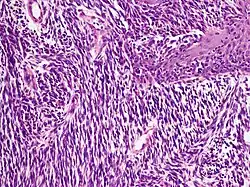

Noduläres Melanom

Aufgrund seines frühen vertikalen Wachstums erreicht diese Form des Melanoms schnell eine große Tiefenausdehnung. Seine Entstehung aus einem gutartigen melanozytären Nävus gilt als selten, eher wird vom nodulären Melanom als gemeinsamer Endzustand zunächst oberflächlich wachsender Melanome mit kurzer horizontaler Wachstumsphase ausgegangen.

Entsprechend seiner nodulären (knotigen) Konfiguration zeigt sich histologisch ein halbkugelig vorgewölbter, oft asymmetrisch angelegter Tumor, der durch eine abgeflachte, häufig auch ulzerierte Epidermis überkleidet wird. Ist die Epidermis erhalten, weist sie in der Regel eine epidermale Melanomkomponente auf, die die dermale Komponente seitlich je nach Lehrmeinung nicht oder maximal über drei angrenzende Retezapfen überragt.

Die dermale Komponente besteht aus einem soliden knotigen Verband oder kleinen Nestern atypischer Melanozyten mit verdrängendem Wachstum zur Tiefe. Die Zellen sind zumeist groß und rundlich, aber auch Spindelzellen, kleine nävusartige Zellen und mehrkernige Riesenzellen kommen vor. Obwohl die Tumorzellen bei geringer Vergrößerung relativ gleichförmig wirken können, zeigen sich bei hoher Vergrößerung in Größe, Form und Chromatingehalt (Chromatin: genetisches Grundmaterial des Zellkerns) variable Zellkerne mit deutlich sichtbaren Nukleolen. Mitosen finden sich auch in tiefen Anteilen der dermalen Komponente. Der Zytoplasmagehalt der Melanozyten ist im Verhältnis zur Kerngröße niedrig und das Zytoplasma enthält unterschiedlich große oder auch als puderstaubartig bezeichnete Melaningranula. Eine Ausreifung der Melanozyten zur Tiefe fehlt.

In der angrenzenden Dermis bestehen ein mehr oder weniger dichtes Infiltrat aus Lymphozyten und Melanophagen, Fibroplasie (Bildung faserigen Bindegewebes) und erweiterte Blutgefäße.[45]

- Noduläres Melanom

-

Noduläres Melanom: halbkugelig vorgewölbter Tumor -

Noduläres Melanom: große Tumorzellen mit vielgestaltigen Zellkernen